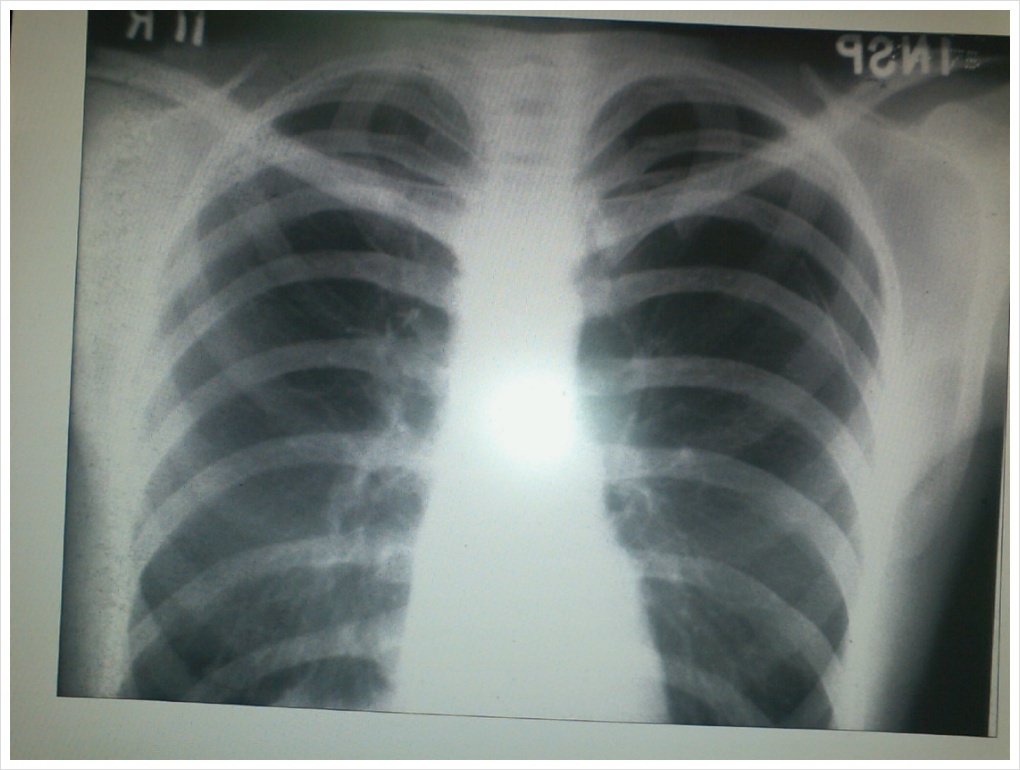

갈비뼈 금이 갔을 때 빨리 낫는 법

갈비뼈 금이는 근육이나 뼈 주변의 조직이 갈비뼈와 분리되는 상태로, 통증과 불편을 유발할 수 있습니다. 이러한 상황에서 빨리 회복하는 방법과 조심해야 할 사항에 대해 알아보겠습니다.